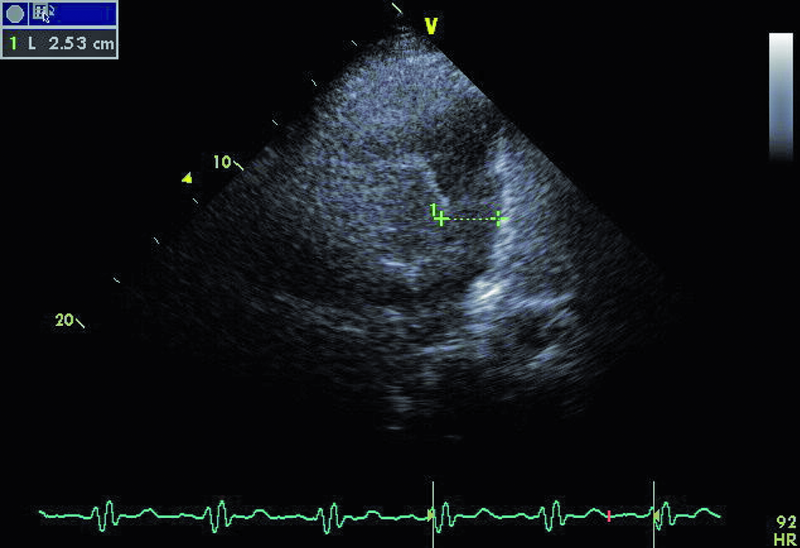

Droga odpływu prawej komory u opisanego chorego jest szeroka i z pewnością nie stanowi zapory dla przepływającej krwi (ryc. 1). Częstym powikłaniem całkowitej korekcji tetralogii Fallota, zwłaszcza z wykorzystaniem łaty przezpierścieniowej, jest duża niedomykalność zastawki płucnej, którą stwierdzono również u opisanego chorego. Strumień niedomykalności w badaniu kolorowego doplera jest szeroki i pokrywa prawie cały przekrój drogi odpływu (ryc. 2). Niedomykalność zastawki płucnej trudno ocenić ilościowo za pomocą techniki ultradźwiękowej. Złotym standardem diagnostyki jest rezonans magnetyczny, który pozwala określić tzw. frakcję niedomykalności. Spośród parametrów echokardiograficznych najbardziej zbliżonym i dość wiarygodnie odzwierciedlającym stopień niedomykalności zastawki płucnej jest czas połowicznego zmniejszenia gradientu ciśnień między pniem płucnym a prawą komorą (pressure half time, PHT). PHT krótszy niż 100 ms świadczy o istotnej niedomykalności zastawki płucnej (ryc. 3). Innym, nieanalizowanym w ilustracjach parametrem może być tzw. indeks niedomykalności, czyli iloraz czasu trwania fali zwrotnej płucnej do czasu trwania rozkurczu. Niedomykalność zastawki płucnej, nawet tak duża, jak w opisanym wypadku, nie musi istotnie ograniczać tolerancji wysiłku. W takiej sytuacji obowiązuje jednak precyzyjna ocena wielkości i funkcji prawej komory serca. Stopień powiększenia prawej komory u tego chorego jest umiarkowany (ryc. 4), a funkcja kurczliwa mięśnia mierzona za pomocą prędkości skurczowej ruchu bocznej części pierścienia trójdzielnego (S’) jest prawidłowa (ryc. 5). Dodatkowym parametrem łatwym do uzyskania niezwykle czułym w określaniu niedomogi prawej komory jest pole prawego przedsionka. Niewielkie przekroczenie górnej granicy normy, czyli 18 cm2, rejestrowane w tym przypadku (ryc. 6) potwierdza słuszność wyboru strategii zachowawczej. Chory może być nadal obserwowany, chyba że warunki anatomiczne drogi odpływu prawej komory pozwalają na przezcewnikową implantację zastawki Melody lub Edwards-Sapien. Określenie możliwości przeprowadzenia tego rodzaju interwencji ponownie wymaga jednak odniesienia się do wyników rezonansu magnetycznego lub wykonania cewnikowania serca.